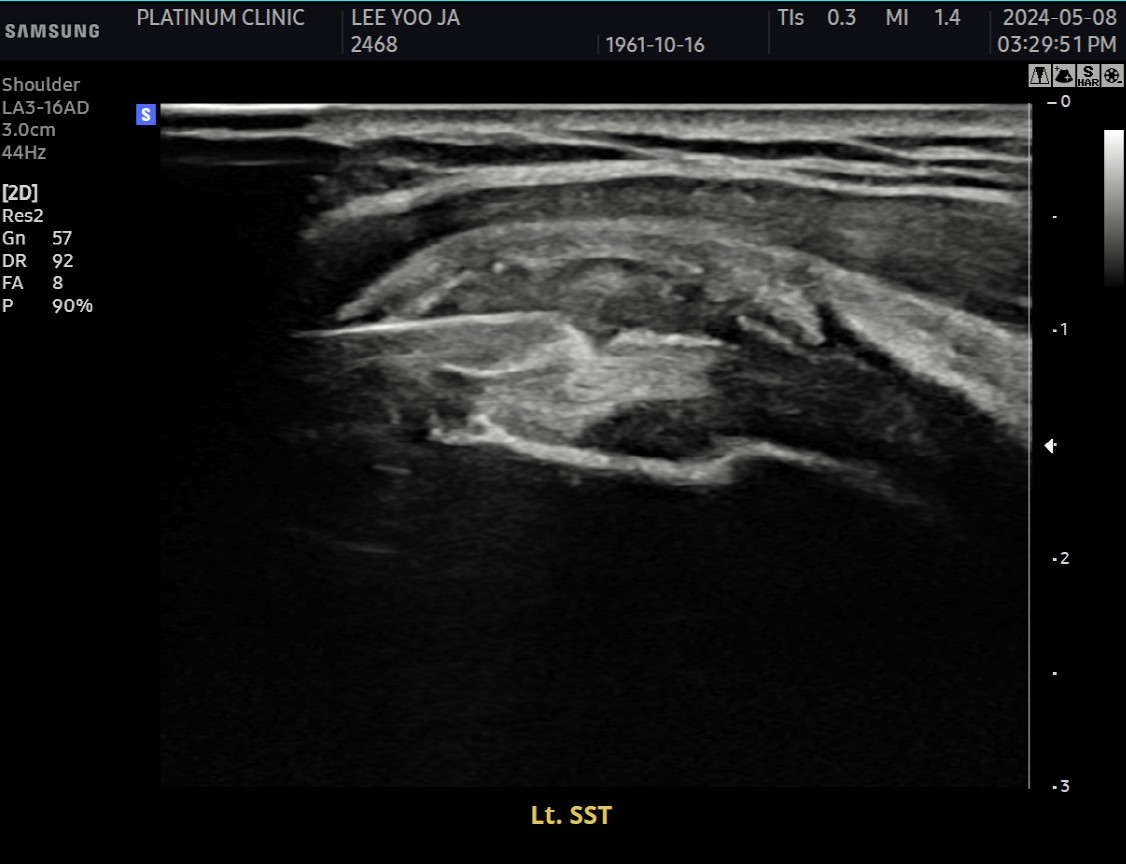

1) 당장의 문제 해결: 관절수액팽창술

먼저 관절수액팽창술로 굳은 관절낭을 풀어드렸습니다.

2) 근본적인 문제 해결: 석회분쇄흡입술

근본 원인인 석회를 제거했습니다. 초음파로 확인된 미세석회들을, 석회분쇄흡입술을 통해 힘줄 사이사이에서 씻어내듯 제거했습니다.

6개월 후, 재발 없이 완치

원장님, 이번엔 진짜 괜찮아요. 예전엔 몇 달 지나면 또 뻣뻣해졌는데, 지금은 그런 느낌이 전혀 없어요.

초음파 검사에서도 석회는 깨끗이 사라졌고, 관절낭 유착도 재발하지 않았습니다.

불씨를 꺼냈으니, 불꽃이 다시 붙지 않은 것입니다.